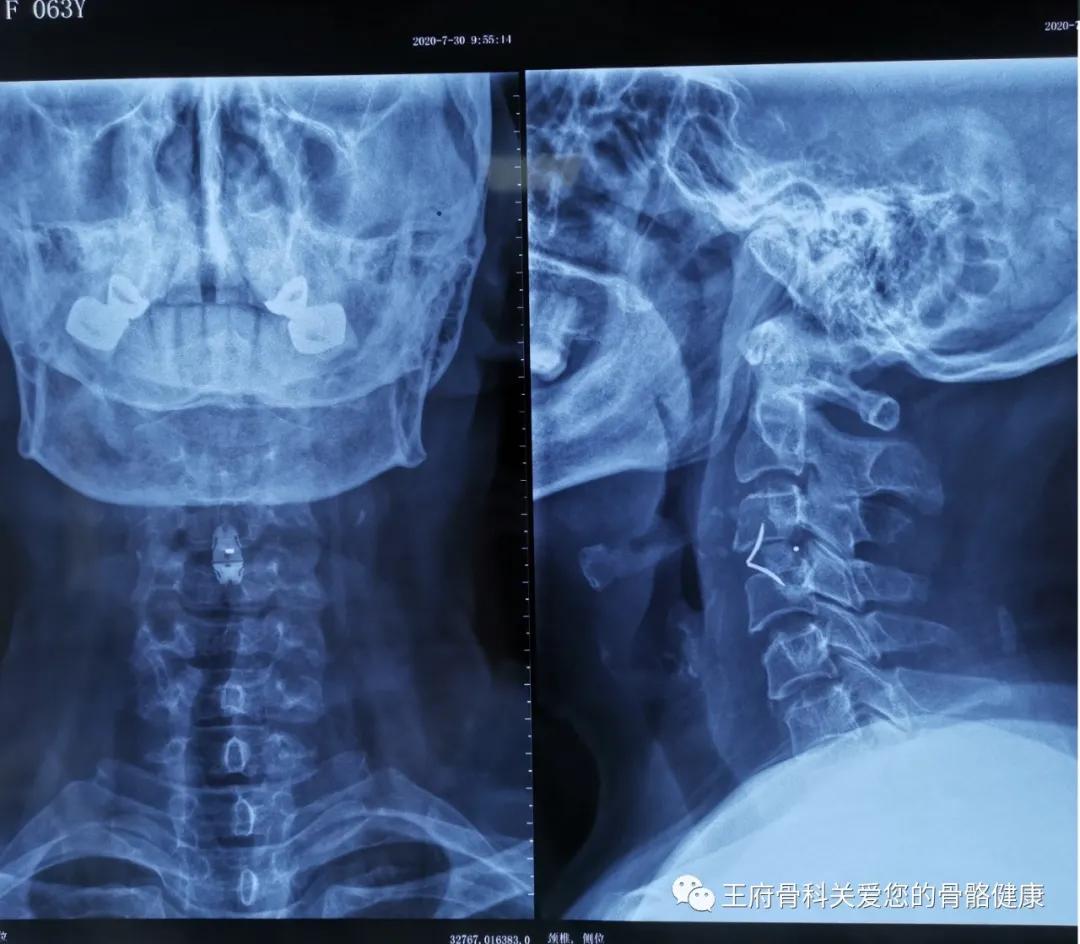

(术后X线片)

当天下午在全麻插管下,急诊科为患者进行颈椎前路椎管减压,郑主任主刀切除突出的C3-4椎间盘并进行固定融合手术,手术在骨伤科、急诊科、麻醉科、心内科等多学科的协助和配合下顺利完成,术后患者生命体征平稳,转入ICU继续观察治疗。2天后,患者已经没有呼吸困难的症状,能够正常下地行走,在家属的陪伴下顺利出院。